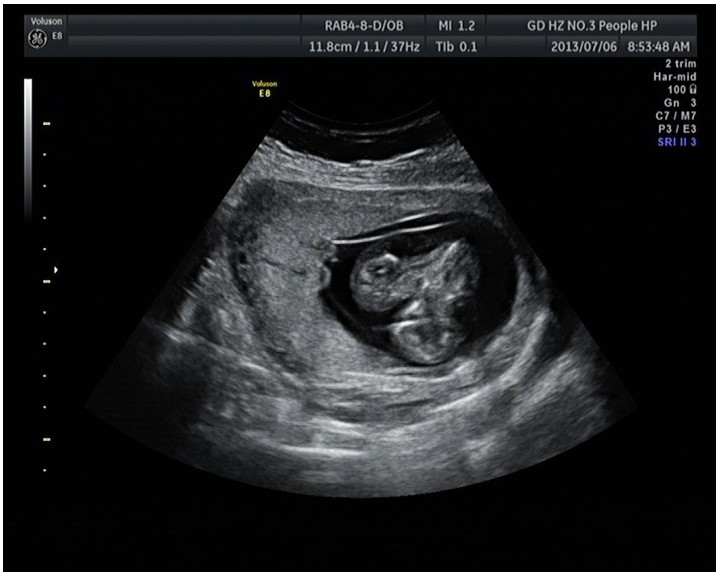

隨著環(huán)境污染日益嚴(yán)重,隨著各種地溝油的誕生,隨著各樣鎘大米的泛濫……我們的健康越來(lái)越受到威脅,很多疾病也隨之接踵而至,胎兒先天性疾病也越來(lái)越多見(jiàn)。7月6日,我院超聲科王瑤醫(yī)生在做胎兒產(chǎn)前NT篩查中發(fā)現(xiàn)一例孕約11周+的聯(lián)體雙胎。超聲所見(jiàn):增大的子宮內(nèi)可見(jiàn)聯(lián)體雙胎兒回聲,可見(jiàn)兩個(gè)胎頭不能分離,胸部及腹部融合,可見(jiàn)一個(gè)增大的心臟。

聯(lián)體嬰兒B超圖像